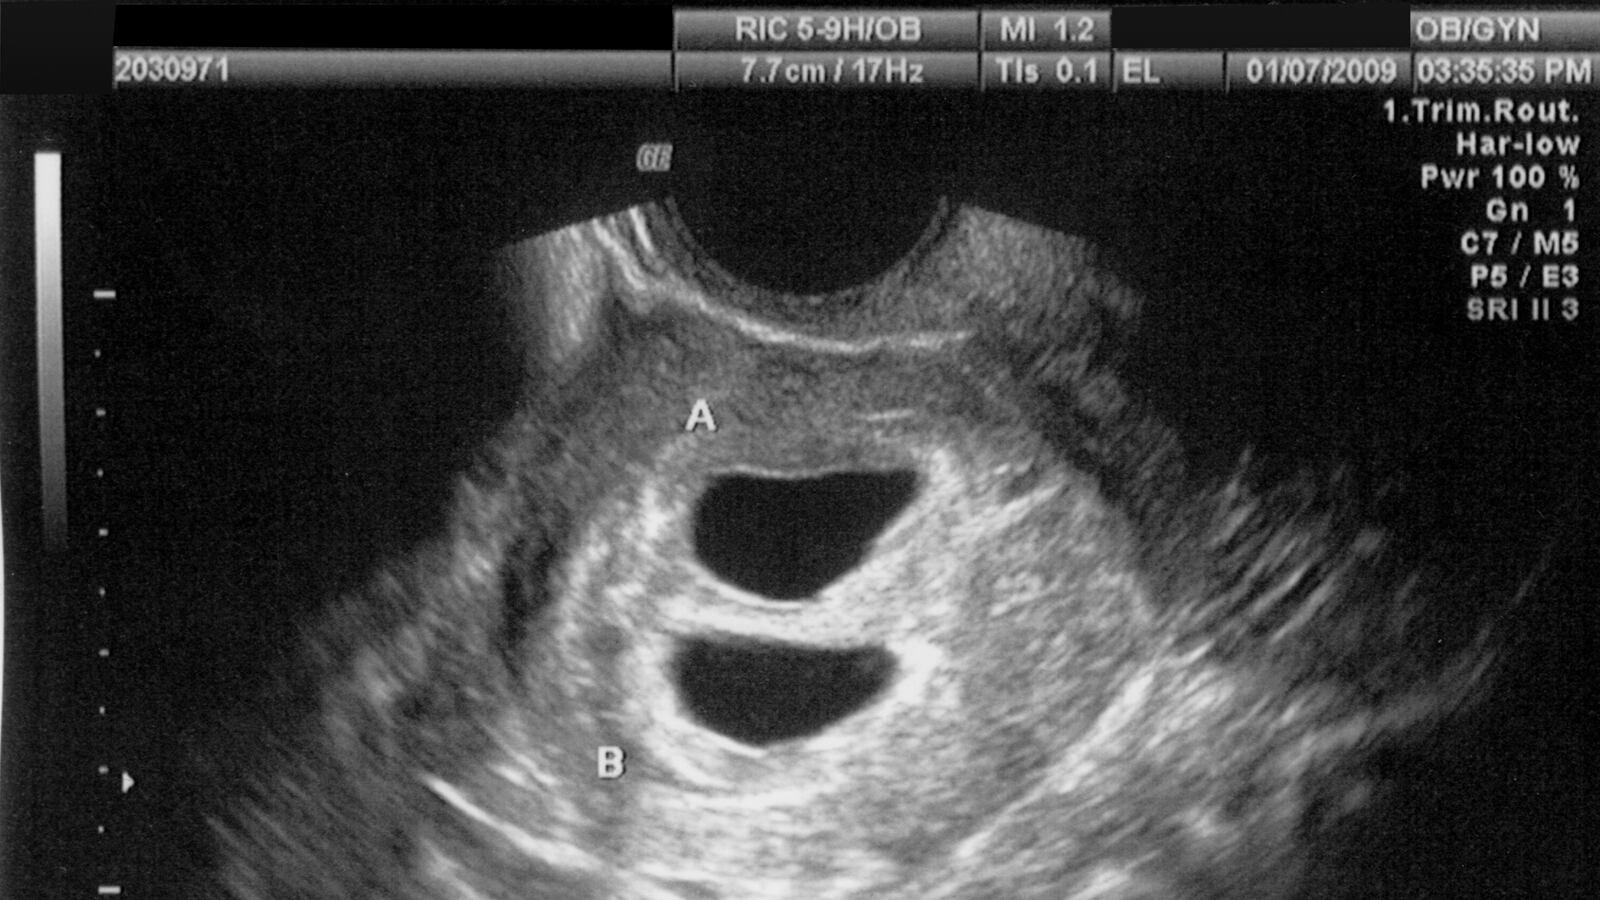

You mean both women and doctors have constitutional rights? A federal judge declared illegal on Friday a North Carolina law that required women who wanted an abortion to first have an ultrasound and then have a medical provider describe the image to them. U.S. District Judge Catherine Eagles ruled that the law is a violation of constitutional free-speech rights because states do not have the right to force health care providers to bear an “ideological message in favor of carrying a pregnancy to term.”